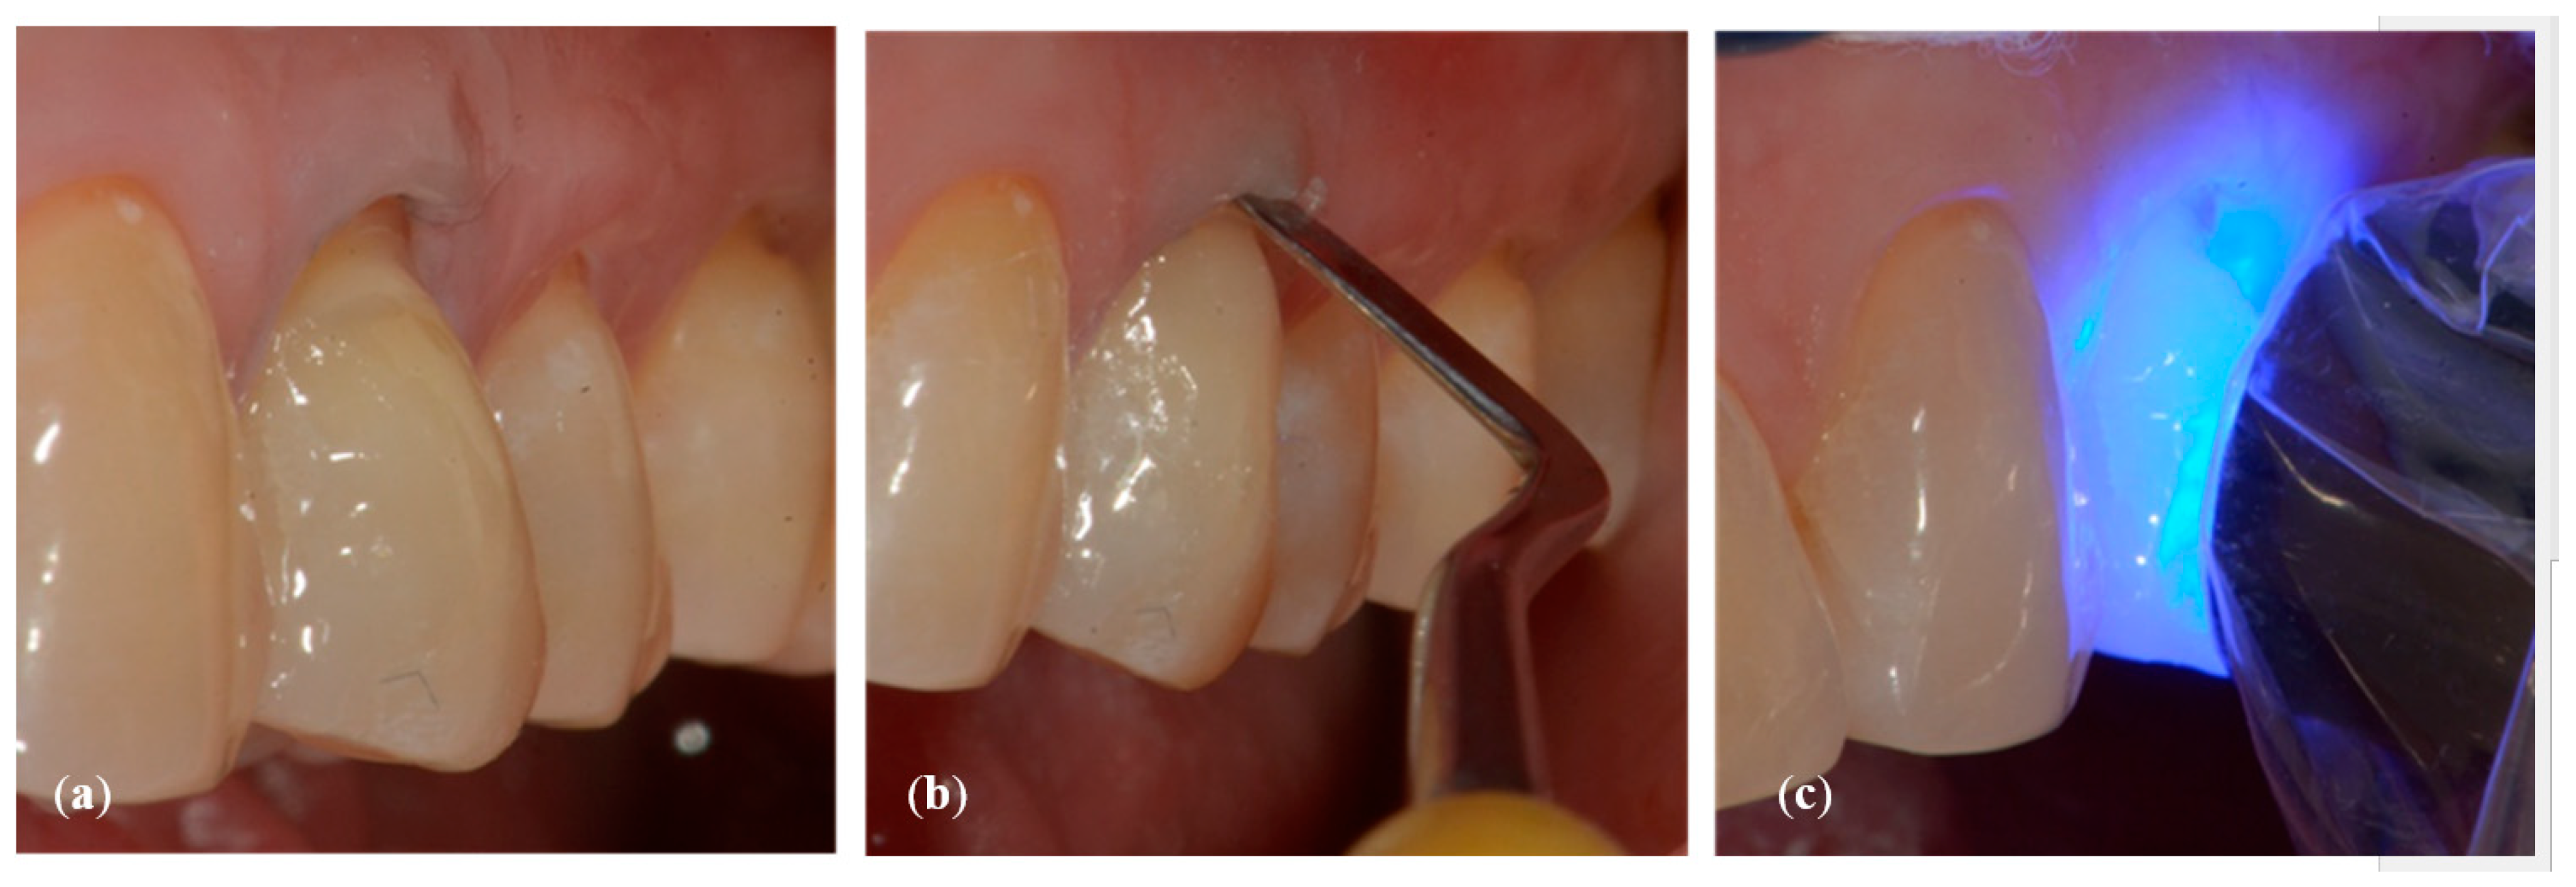

- Initial measurement of the length of the clinical dental crown (performed with a millimeter periodontal probe placed adjacent to the dental crown and having as a reference the most apical part of the gingival sulcus and the highest part of the crown) and photography of the lesions at time 0 (t0) (Figure 2a).

- Application of a thin layer of flowable composite (3M Filtek Supreme flowable, 3M Italia Srl,Via Norberto Bobbio, 21, 20096 Pioltello (MI) Italy) on the bottom of the cavity and of composite (3M Filtek Supreme XTE, 3M Italia Srl,Via Norberto Bobbio, 21, 20096 Pioltello (MI) Italy), on top and perimeter seal, by means of a layering procedure. The composite was applied in horizontal excess following the principles of the BOPT technique, trying to emphasize the cervical convexity. The polymerization phases were performed using the KERR (KERR ITALIA SRL,Via Passanti 332 84018 Scafati, Italia) 800 Watt lamp for 20″ for each layer [23] (Figure 6a–c).